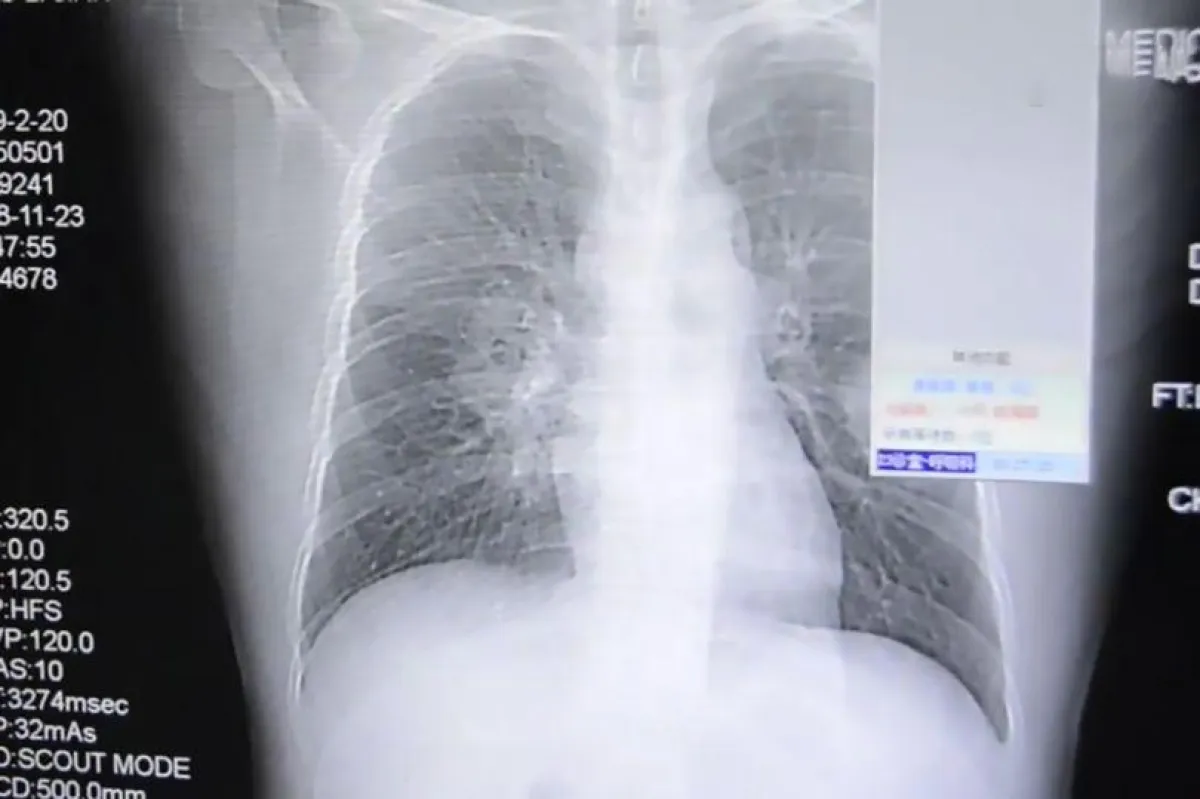

وقد أُدخل الرجل إلى المستشفى بالطوارئ، حيث أكدت الأشعة السينية أنه يعاني من التهاب شديد في الرئة، وأكدت التقارير الطبية أن سبب ذلك هو استنشاقه المتكرر لجواربه الخاصة، وقد أُبقي هذا الرجل في المستشفى للعلاج.